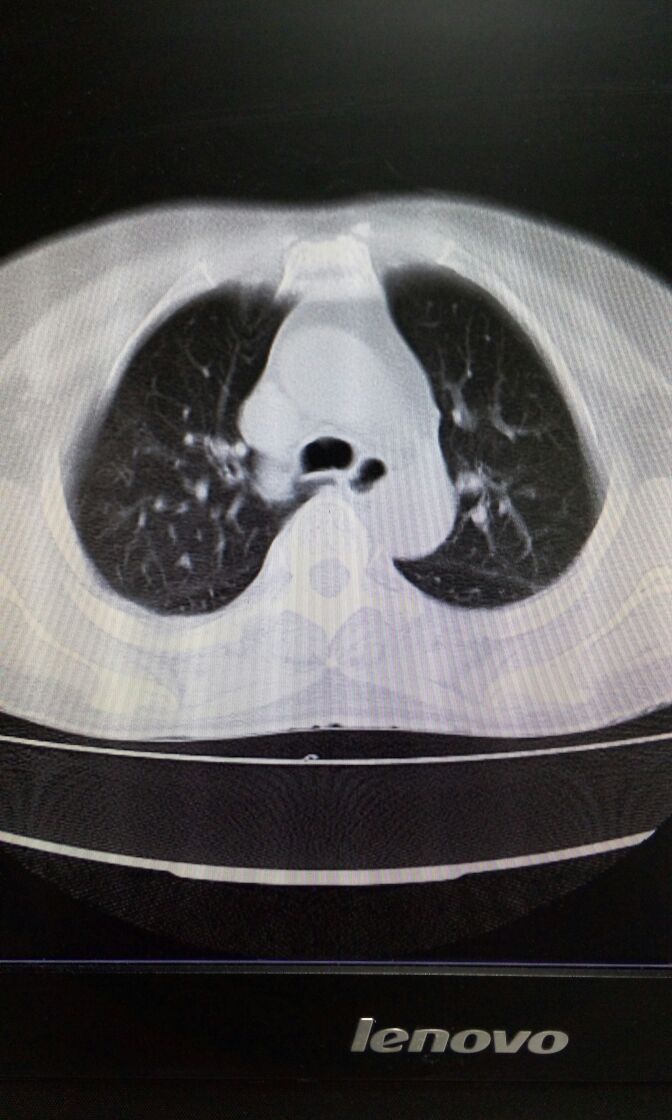

女,65岁,头痛、发热畏寒伴咳嗽咳痰1周。咽拭子流感A抗原阳性。肺部CT如图。诊断和治疗?

女,65岁,头痛、发热胃寒伴咳嗽咳痰1周。咽拭子流感A抗原阳性。肺部CT如图。诊断和治疗?补充纵膈窗